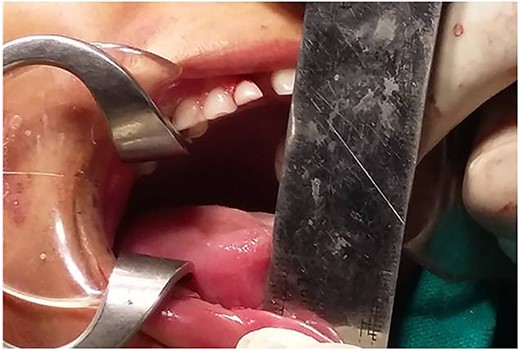

A surgical treatment of gap arthroplasty with interpositional temporalis myofascial flap on right TMJ was planned under general anesthesia. In order to approach the TMJ area, a pre-auricular incision was utilized [8, 9]. The incision in shape of big question mark avoiding injury to the superfacial temporal vessels and facial nerve was made till the shining surface of temporalis fascia and dissection preceded in this plane to zygomatic arch and extended anteriorly and posteriorly to expose the limits of the ankylosis. Thereafter periostium over the zygomatic arch and the ramus incised and elevated (Fig. 4). After an adequate exposure of site of bony block, bone was removed by using a round bur until a thin cortical bone was left in the depth. To prevent injury to internal maxillary artery or pterygoid plexus of veins, a malleable retractor and surgical burs at slow speed were used. The joint cavity was then irrigated with betadine and irregular edges of segments were shaved by surgical bur and disconnected completely the ramus from the upper bony block (Figs 5 and 6). In this case, glenoid fossa was recontoured as much as anatomical as possible. A gap of at least 1.5 cm was created between glenoid fossa and mandible followed by insertion of interpositional temporalis myofascial graft (Figs 7 and 8). Zygomatic arch osteotomy was also performed, which immensely eased the coronoidectomy procedure but added to complexity of the surgery and fixation hardware had to be used in addition to fix the arch back into its position.

Mouth opening of ~37 mm was done using Hister’s jaw opener at time of surgery (Figs 9 and 10). Suction drain was placed, and the flap was sutured using 3–0 vicryl for deeper layers and skin was closed using 4–0 prolene.